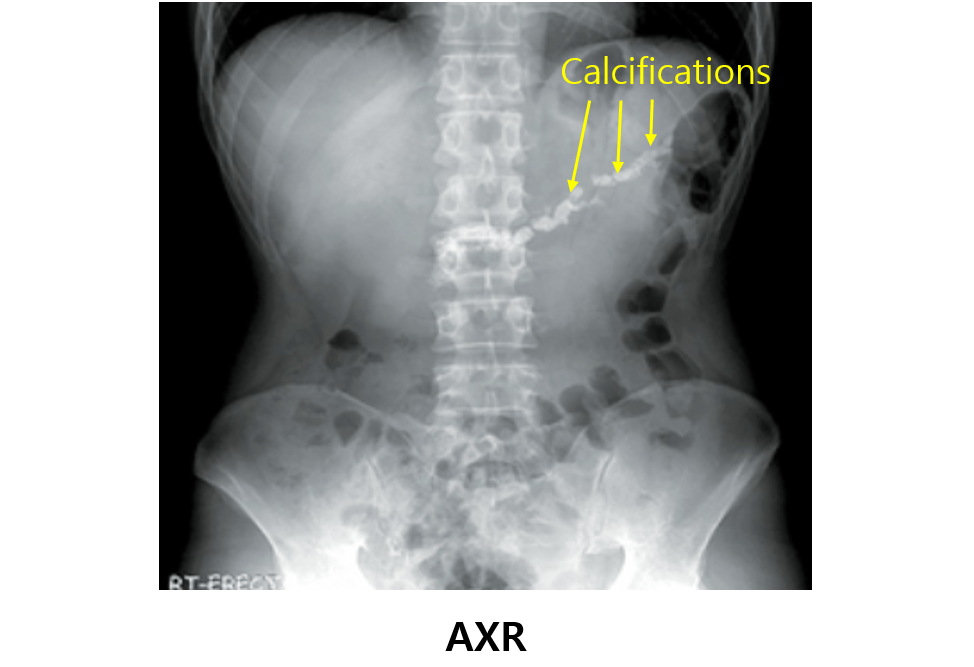

급성 췌장염과 비슷하지만 만성화된 복통의 양상과 설사 및 지방변이 특징적이다. Amylase/lipase가 정상인 경우가 많다는 점을 주의해야 하며, AXR이나 CT에서 췌장에 석회화를 보인다는 것이 주요 특징이다. 치료는 진통제와 췌장효소제를 이용한다는 것이 중요하다.

(1) AXR: Pancreatic calcifications

(2) CT: Pancreatic calcifications, pancreatic duct dilatation, atrophic pancreas

• AXR/CT: Pancreas calcification